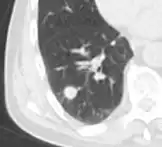

Low attenuating nodule (in this case a fat containing hamartoma).[9]

Cavitation with relatively thick wall, in this case aspergilloma).[9]